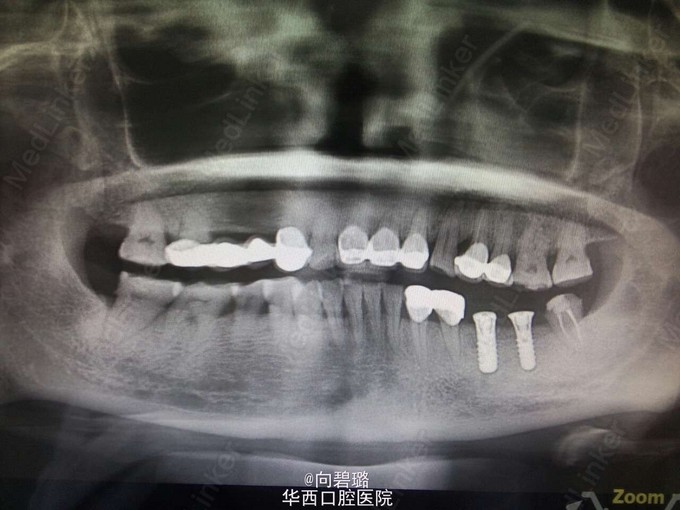

主诉:左上后牙疼痛1周。 现病史:1年前在外院曾行根管治疗手术,并行烤瓷冠修复,手术后无不适,一周前开始出现牙齿疼痛。

24、25牙烤瓷冠,26、27牙磨耗严重,冷(-),叩(+),无明显松动,无持续性疼痛,唇侧牙槽嵴粘膜处未见窦道;26牙叩(+),冷(-),松(-)。 电活力测试值27牙为9,26牙为8. 全景示:24牙根管内充填影像,25牙根尖暗影,26牙近中根尖暗影。

诊断:24牙根尖周炎;25牙根尖周囊肿 治疗方案:24牙显微镜下根管再治疗;25牙根管治疗。 建议患者根管治疗后,观察一段时间,若根尖炎症消除则行桩冠修复